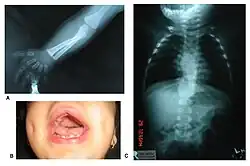

Zespół Robinowa (ang. Robinow syndrome) – rzadki zespół wad wrodzonych, charakteryzujący się niskorosłością, skróceniem kończyn, cechami dysmorficznymi twarzy i głowy, nieprawidłowościami zewnętrznych narządów płciowych i wadami budowy kręgosłupa. Zespół opisał jako pierwszy w 1969 genetyk Meinhard Robinow i lekarze Frederic N. Silverman oraz Hugo D. Smith, na łamach American Journal of Diseases of Children[1]. Do 2002 roku udokumentowano ponad 100 przypadków zespołu Robinowa.